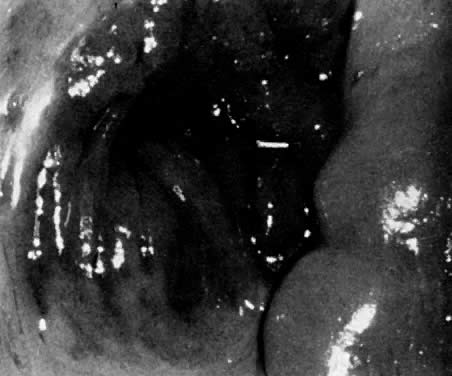

The most common indication for CO2 laser surgery in the lower genital tract is the treatment of condylomata acuminata.21 These lesions caused by the human papilloma virus (HPV) are most commonly found on the vulva and perianal skin. Although genital warts can cause irritation and some discomfort, they are not generally painful; most patients seek medical attention because of their unsightly growth. They spread principally by autoinoculation of the HPV virus and may undergo spontaneous regression. Pregnancy, oral contraceptive use, diabetes, immunosuppressive drug therapy, and immunodeficiency virus infections can accelerate growth of genital warts. These lesions may be polypoid, flat, papillomatous, fleshy, white, or pigmented in appearance. The indication for CO2 laser ablation of genital warts is the presence of gross disease, and not subclinical HPV infection, such as koilocytosis and papillosis.

Local anesthesia may be used for small isolated vulvar warts. However, with more extensive disease, general anesthesia is preferred. Warts should be vaporized no deeper than the level of the surrounding skin surface (Fig. 21, Fig. 22, and Fig. 23) using a power level of 40 W to 60 W with a beam diameter of 3 mm. After complete vaporization of the genital warts is accomplished, the 1 cm to 2 cm of skin surrounding the individual lesions is brushed lightly with 10 W of power and a 2-mm-diameter spot size to destroy subclinical HPV involvement and diminish the recurrence of the disease. When the condyloma lesion has a well-defined pedicle, it is more efficient to excise rather than vaporize the entire lesion. Ablation of the remaining base is then accomplished to the level of the skin surface. The postoperative treatment regimen is identical to that described for VIN. Laser treatment of genital warts is effective; they are eliminated in over 90% of patients. For those patients who are immunologically compromised, chronic application of 5-fluorouracil cream has been recommended.22 The use of recombinant interferon after laser treatment by Reid and colleagues has also diminished their recurrence.23

Fig. 21. Condylomata acuminata are vaporized, sparing normal intervening skin. Vaporization is carried to a level of surrounding skin.

Fig. 22. Extensive warts are vaporized completely under general anesthesia.